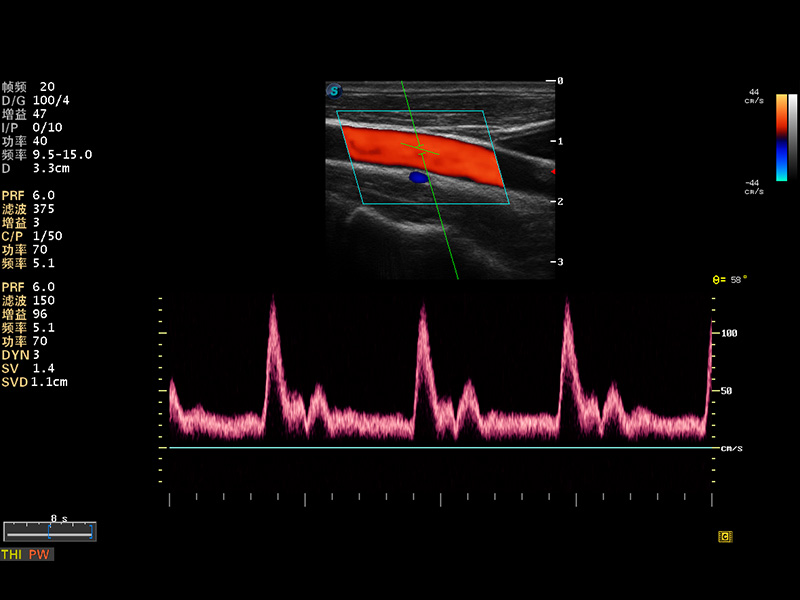

S8 EXP便携式彩色多普勒超声诊断仪是银河优越会研发的高端全身应用型便携彩超。高通道的VIS平台融合可视化(Visual)、智能化(Intelligent)和人性化(Smart)的特点,配以银河优越会自主研发生产的探头大家族,使您能够快速、准确的获得病人信息,提高工作效率的同时减轻疲劳。

多波束形成器

谐波成像